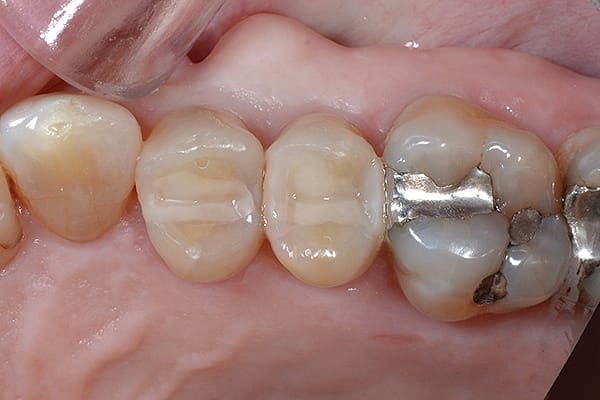

1. (Case 1) Preoperative view of tooth No. 29. Upon clinical examination, caries on the disto-occlusal was noted; a bitewing radiograph confirmed the need for an interproximal restoration.

2. After successful anesthesia using 4% Articadent® with epinephrine 1:200,000 (DENTSPLY Pharmaceutical), a Palodent® Plus WedgeGuard (DENTSPLY Caulk) was inserted and the Class II preparation on tooth No. 29 was completed. Note that tooth No. 30 was a porcelain-fused-to-metal (PFM) crown and the WedgeGuard helped prevent iatrogenic damage to the mesial aspect, allowing for faster preparation without the stress of damaging/repolishing the adjacent tooth.